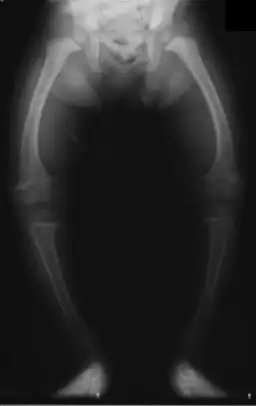

![]() Radiografía de las piernas en un niño de 2 años de edad con raquitismo | ||

Genu varo es una deformidad frecuente de las rodillas en niños, secundaria a la posición intrauterina (también llamado piernas arqueadas y tibia vara), cuya forma fisiológica se corrige por lo general con el desarrollo normal del niño. Sin embargo, cuando este persiste más allá del segundo año puede ser patológico.[1] Es importante diferenciar el proceso fisiológico de la enfermedad de Blount (tibia vara), que es una peculiaridad física[2] marcada por una inclinación hacia afuera de la pierna en relación con el muslo, dando la apariencia de un arco. Por lo general, la angulación medial de ambos, el fémur y la tibia, está involucrada.